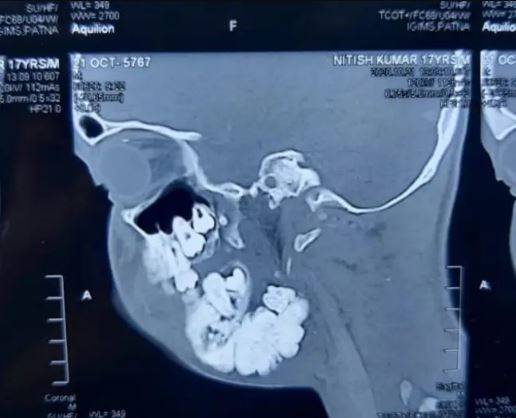

印度一名17歲男子於5年前發現下頜骨長有腫瘤,令他生長出超過82顆牙齒。近日他終接受3小時手術,切除多餘牙齒及腫瘤。

17歲少年Nitish Kumar於5年前發現下頜骨兩側長有巨型腫瘤,即複雜性齒瘤(complex odontoma),令其一顆牙齦中可長出多顆牙齒,口腔至今已長有超過82隻牙齒。

可惜Kumar多年來一直缺乏適當治療,病情持續惡化,他的下巴已嚴重腫脹,臉部也因而扭曲。早前他到印度比哈爾邦的醫院求診,醫生Manish Mandal指,若再不清除這些牙齒,腫瘤可能會轉變為惡性。